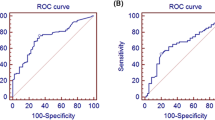

The spearman analysis, shown in Table 3, showed that the plasma Lp-PLA2 level was positively correlated with mean TFC (r = 0.790, P<0.001) and C-reactive protein (CRP), (r = 0.179, P = 0.019), and negatively correlated with HDL-C (r = − 0.693,P<0.001) and ejection fraction (r = − 0.164, P = 0.033) (Figs. 3, 4). Univariate and multivariate logistic regression analyses were used to explore the associations of risk factors with CSF. The results indicated that the level of Lp-PLA2 (OR = 1.049, CI = 1.034–1.064, P < 0.001), male sex (OR = 2.192, CI = 1.161–4.140, P = 0.016) and hypertension (OR = 1.965, CI = 1.034–3.736, P = 0.039) were risk factors for CSF. After adjustment for traditional confounders, we found that the Lp-PLA2 levels remained to be significantly and independently associated with the presence of CSF (OR = 1.040, CI = 1.022–1.059, P<0.001) (Table 4, Table 5, Fig. 5).

The ROC curve analysis (Fig. 6) showed that Lp-PLA2 (AUC values = 0.978; CI = 0.959–0.993; P < 0.0001) was better in predicting CFS than TC (0.621; CI = 0.537–0.706; P = 0.0064), TG (0.603; CI = 0.518–0.688; P = 0.021), male sex(0.592; CI = 0.506–0.677; P = 0.040)and hypertension (0.576; CI = 0.503–0.645; P = 0.036). The sum of the sensitivity and specificity for the prediction of the extent of CSF was maximal at a level of Lp-PLA2 ≥ 260.5 ng/ml (sensitivity = 76.9% [95% CI 66 to 85.71%], specificity =98.9% [95% CI 94.1 to 99%]).